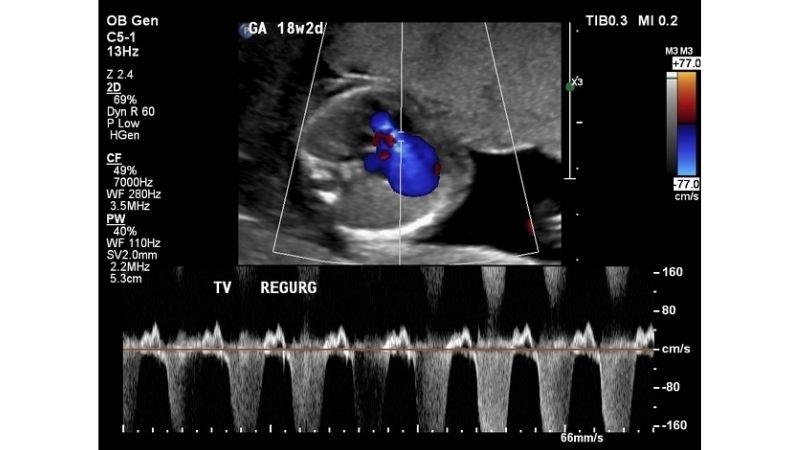

Images visual examples of Tricuspid Regurgitation (Insufficiency)

Visual examples often show an enlarged right atrium and ventricle, with abnormal blood flow patterns detected through echocardiography. These images help illustrate the mechanical dysfunction that contributes to the disease.

Tricuspid Regurgitation Diagnosis confirmed with echocardiogram

Tricuspid Regurgitation Echo helps measure severity